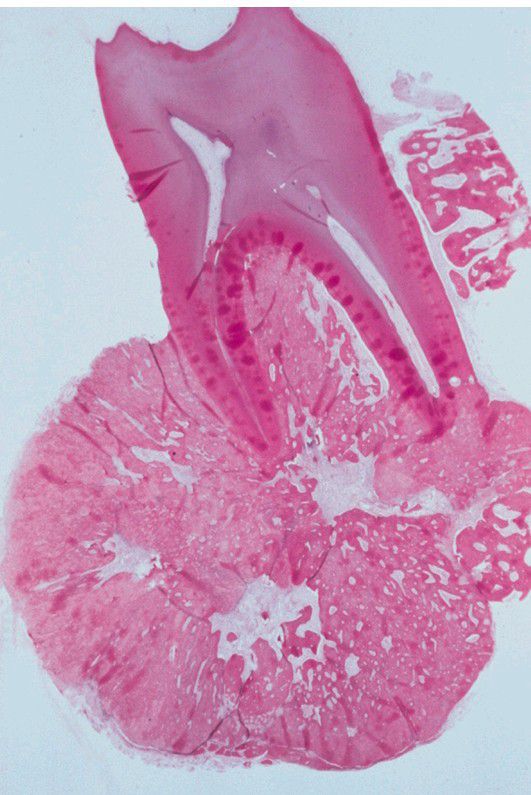

Cementoblastoma

. Low-power photomicrograph showing the tumor attached to the roots of the tooth.

Tumor

Rootapex